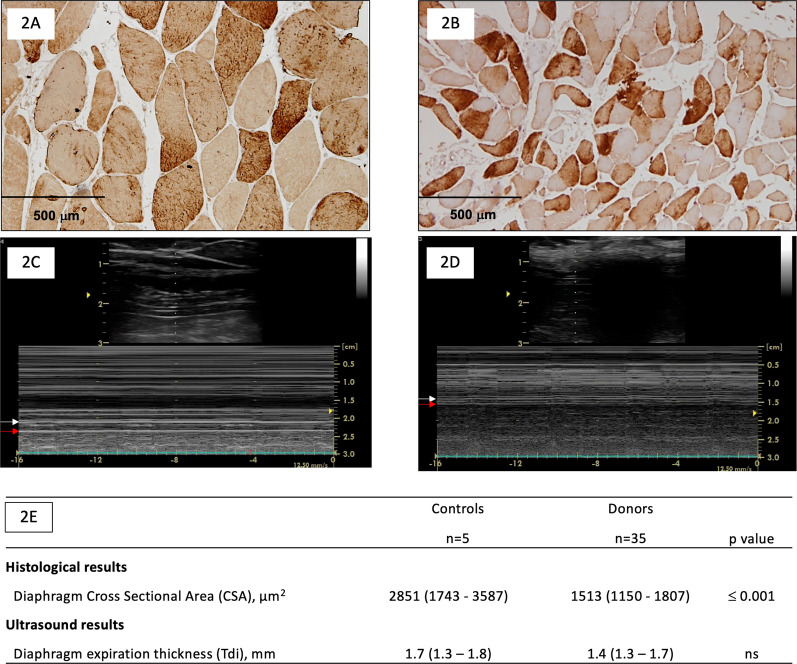

Diaphragm cross-sectional area

The size of diaphragmatic fibers was significantly lower in donors than in controls [1513 (1150–1807) μm2 vs 2851 (1743–3587) μm2, p ≤ 0.001] (Fig. 2A, B and E). The median CSA value in the control group (2851 μm2) was used as a threshold to define diaphragm atrophy.

Diaphragm cross-sectional area (CSA) and diaphragm expiratory thickness (Tdi) related data in donor and control groups. A and B Representative examples of histological samples. C and D Representative examples of ultrasound measurements. White arrow: pleural layer; red arrow: peritoneal layer. E Principal study variables (histological and ultrasound) in control and donor groups. Data are shown as median and interquartile ranges (IQR or 25th–75th percentile)

Diaphragm expiratory thickness (Tdi)

Ultrasound Tdi intra-observer coefficient of variation was 0.93 (CI 0.8–0.96) and 0.96 (CI 0.94–0.98) according to sonographer. Measurements of Tdi showed a good inter-observer agreement between the two observers (Rho 0.89, p ≤ 0.001) as shown in Fig. 3. Tdi was lower in donors than in controls although the difference did not reach statistical significance [1.4 (1.3–1.7) mm vs 1.7 (1.3–1.8) mm, p > 0.05] (Fig. 2C, D and E). The median Tdi value in the control group (1.7 mm) was used as a threshold to define lower Tdi at end-expiration.